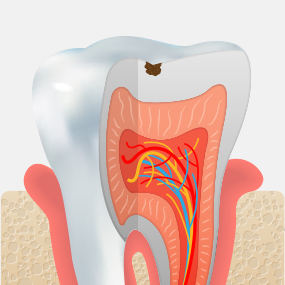

충치가 어느 정도 진행되었는지에 따라 치료 방법은 크게 달라질 수 있습니다. 서울하나치과는 정밀 진단을 통해 치아를 최대한 보존할 수 있는 치료법을 안내해드립니다.

CARIES TREATMENT

치아 겉면인

법랑질의 충치로

통증이 거의 없습니다.